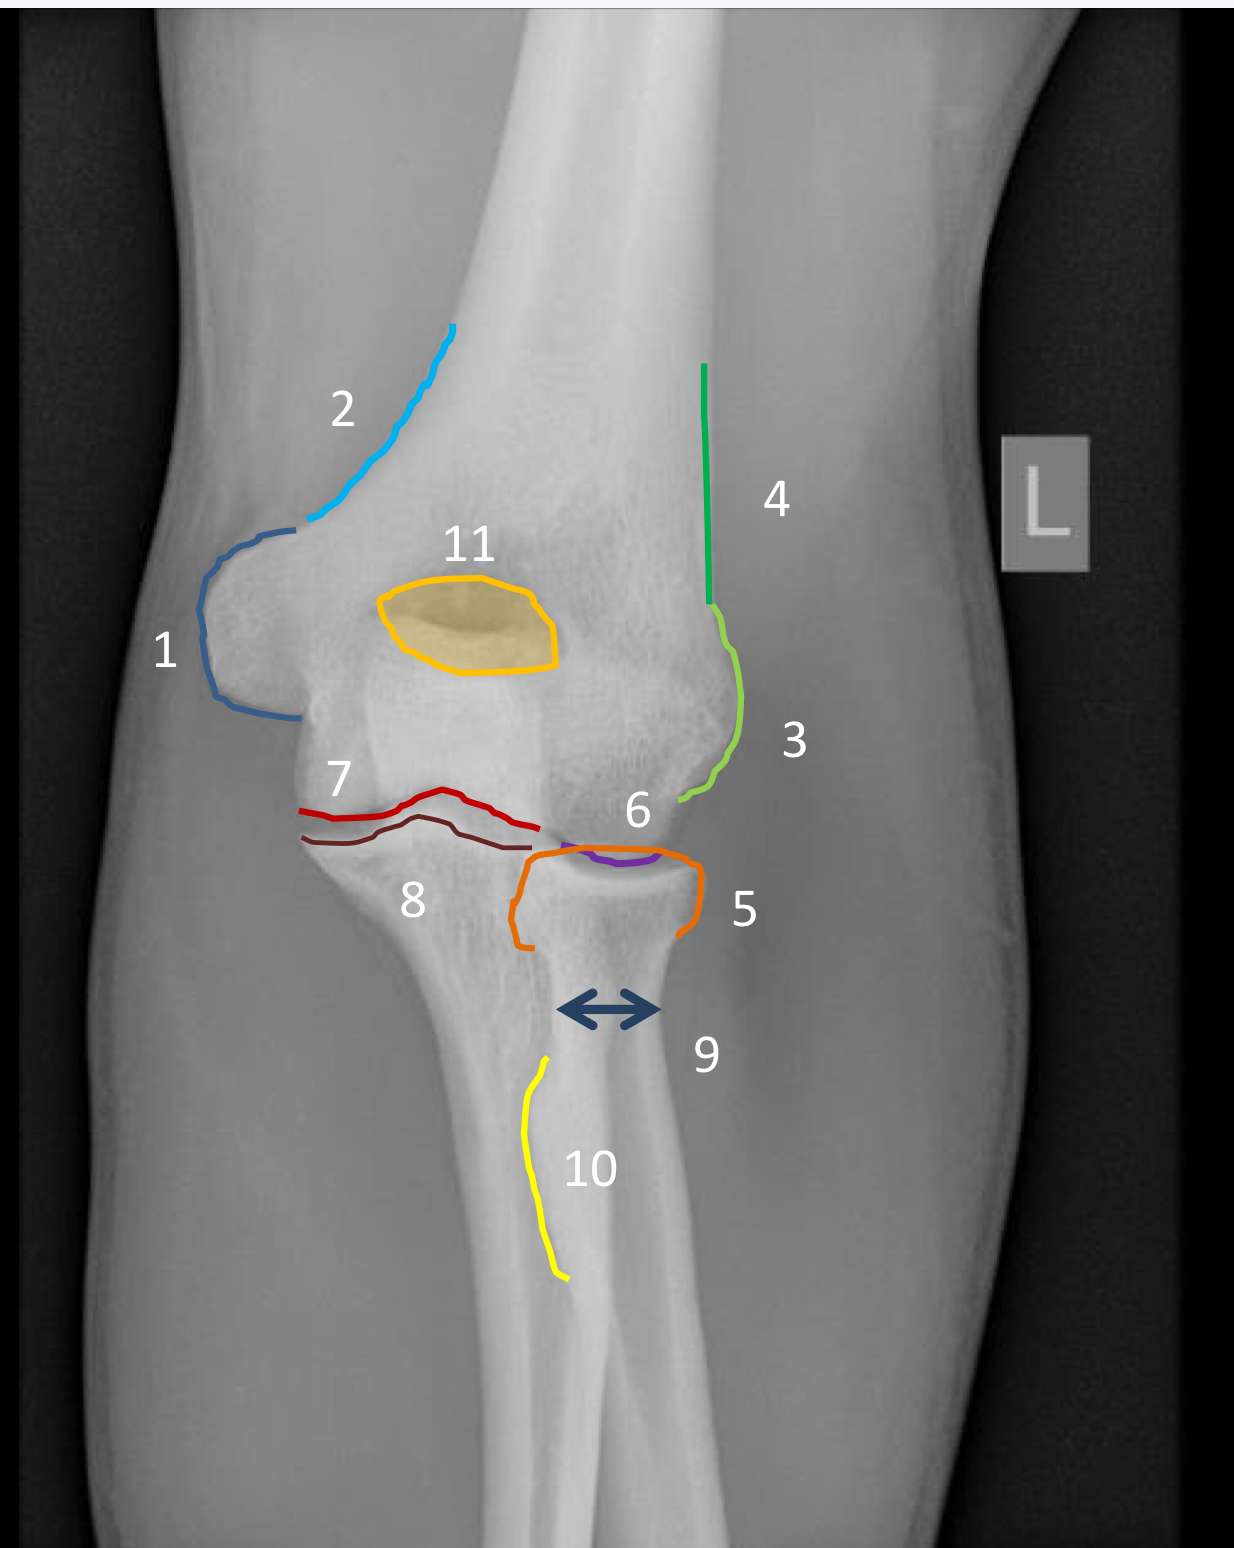

1?

lateral supracondylar ridge

2?

olecranon process

3?

coronoid process

4?

radial tuberosity

5?

radial notch of the ulna